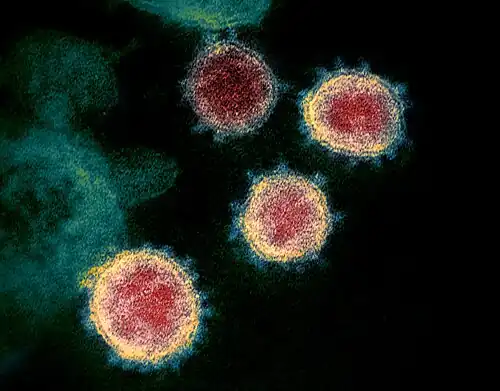

- Microbiology